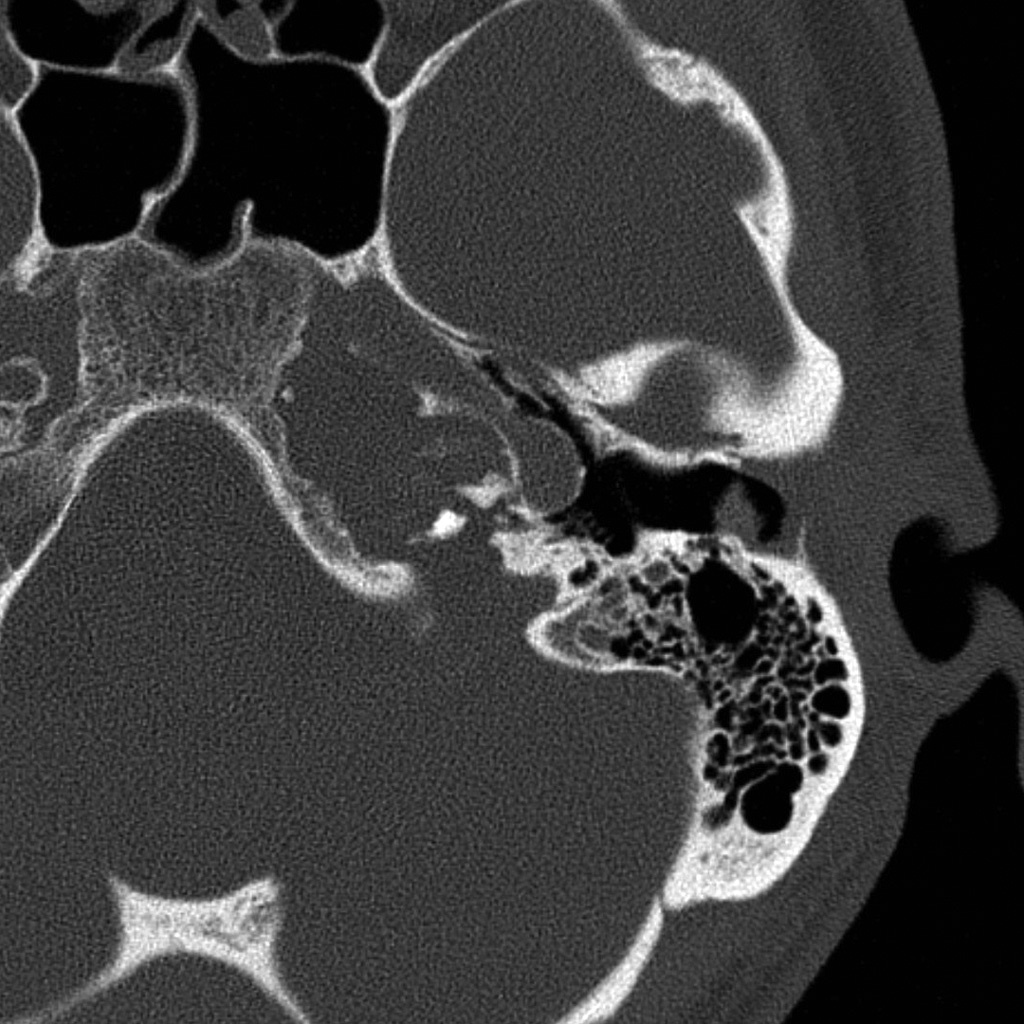

cochlear aplasia

The labyrinth is abnormal with the cochlear absent (cochlear aplasia). The vestibule, semicircular canals and ossicles are present.

Cochlear aplasia, or complete absence of the cochlea is a rare anomaly which accounts for only 3% of cochlear malformations.